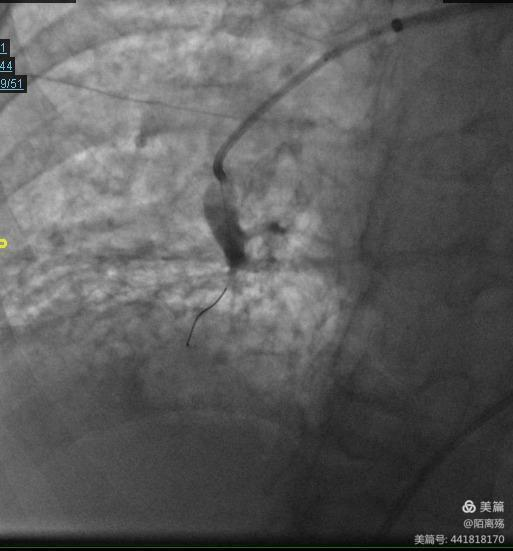

球囊确定在狭窄病变部位后,接上压力泵后,逐渐增加压力使球囊膨胀,切断狭窄血管腔里面网状的血栓,挤压机化血栓至血管壁,达到扩大狭窄肺动脉内的管径面积,增加通畅性,改善肺动脉的血流。

患者经肺血管球囊扩张成形术(BPA)后血氧饱和度由85%上升至93%,右心导管下肺动脉平均压由57降至48mmHg,成功开通病变肺血管血流。